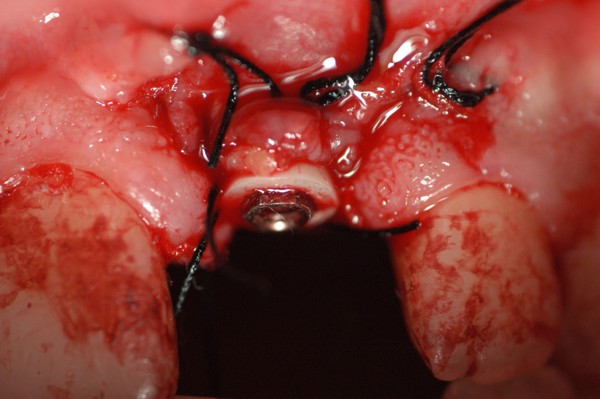

Abstract: Las fuerzas anterógradas traumáticas son en general las causantes de fracturas radiculares en el sector anterior de la boca. Desarrollo: El paciente se presenta a la consulta , con la fractura de una funda de porcelana inyectada en la zona cérvico palatina, solicitando simplemente la reparación en boca para evitar rozamientos linguales. Dicha funda con un perno colado en oro y su correspondiente endodoncia, habían sido realizadas en mi clínica varios años atrás, con un «aparente éxito total». Radiograficamente, se encuentra una fractura radicular cercana al tercio gingival Observada la oclusión de las piezas anteriores, podemos ver que el vínculo ideal de Acoplamiento, no se cumple, habiendo una relación de franco contacto la que ha provocado la fractura. Llevando al paciente a Oclusión en Relación Céntrica, podemos ver el espacio a nivel anterior, correspondiente a la centricidad mandibular. En esa misma posición , es dable percibir una faceta parafuncional mesial del primer premolar superior… …que antagoniza con una faceta parafuncional distal del canino inferior… ..constituyendo un plano inclinado que provoca la antelación mandibular o Discrepancia Horizontal, fracturando la raiz del incisivo central. Extraida la porción coronal de la raiz, pensamos en la realización de un Implante Inmediato, a pesar de la presencia de una fístula dado que se trataba de un central, decisión que obtuvo éxito implantario mas no estético, según veremos luego. Era fundamental conservar lo mas posible las tablas óseas, que de hecho había perdido la porción cervical Realizamos una incisión que conservara las papilas de las piezas adyacentes. Realizamos la exodoncia mediante un instrumento construido «ad hoc» que denomino: Con lo que obtenemos la preservación «ad integrum» de las corticales peridentarias remanentes. Instalamos entonces un implante T.B.R. de 15 mm de largo por 4 mm de diam. con cuello de zirconio de 3,5 mm …quedando tres espiras sin hueso por vestibular, producto de la tabla perdida, Incidimos el periostio a nivel apical del colgajo para obtener mayor paño quirúrgico, y legramos un bolsillo palatino sin incisiones de descarga, para la inserción de la membrana. Suplementamos la carencia ósea vestibular con «BIOSS» …e instalamos una membrana reabsorbible «BIOGUIDE» , que fijamos con el mismo implante, y calzamos por palatino. Suturamos Instalamos nuestra provisional previamente confeccionada, sobre un abuttment de titanio. Y controlamos radiograficamente Pasadas tres semanas del retiro de los puntos, observamos una cicatrización alta que nos muestra el anillo de zirconio del implante. ……………………………………………….. Transcurridos tres meses preparamos una nueva cirugía, dirigida a instalar un injerto autólogo de conectivo en el área del anillo, con un nuevo desplazamiento del colgajo vestibular. Tomamos tejido conectivo del paladar a nivel de los premolares, mediante una incisión mucosa «en libro», y disección del conectivo subyacente. Lo posicionamos en vestibular del anillo de zirconio y lo fijamos mediante sutura Y semanas después nos encontramos con un nuevo fracaso de orden estético. ……………………………………………….. En la actualidad, el caso esta estable , aún con su funda provisional, a la espera de un nuevo intento plástico, mediante Injerto Libre de Encia. ………………………………………………….. ESQUEMA MECÁNICO DEL FENÓMENO …que además de los hechos mostrados en el caso presentado, frecuentemente provocan en el sentido antero posterior los fenómenos de DISPERSIÓN ,en el maxilar superior…y de APIÑAMIENTO en el maxilar inferior. CONCLUSIONES: Además del rigor académico que nos convoca… esta; nuestra casa…nos otorga la confianza que solo da el saber que estamos siempre entre amigos, que cada vez son más. Por tanto es que debo decir: YO fui el responsable de dicha fractura… …porque… …..que hubiera sucedido si hubiera hecho todo el trabajo implantario sin ajustar previamente su oclusión? Seguramente a esta altura del caso…también hubiera fracasado el implante. Siempre decimos que se aprende de los errores más que de los aciertos, y Dr. Carlos A. Acuña Priano

Fig.22(Pie de foto: Membrana)

Fig.24(Pie de foto: funda provisoria en infraoclusión)

Fig.25(Pie de foto: Rx post op.)

Fig.26(Pie de foto: Anillo de zirconio al descubierto)